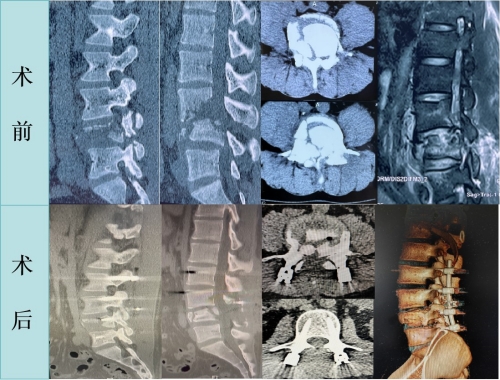

面对如此遭遇小王及家人心急如焚,经多方打听后,来到湘雅三医院急诊就诊。急诊科医师接诊后立即邀请了脊柱外科等专科会诊,邓幼文主任得知消息后,在第一时间赶到急诊查看患者,并详细询问病史、仔细做了体格检查,结合影像学资料,邓幼文主任确认了患者的诊断并提出了个体化的治疗方案。小王诊断为“L3、4锥体爆裂性骨折、L5椎体压缩性骨折、马尾神经损伤、左胫骨干骨折、双下肢静脉血栓形成、糖尿病”。考虑到脊髓受压,需要立即行手术减压,但由于患者车祸外伤后5天才入住,又因血糖过高无法立即手术,此时由于脊髓受碎裂的骨碎片压迫过久,手术治疗的难度较大。然而,基于行医二十余年的丰富经验和对团队默契配合的充分自信,邓幼文主任团队决定迎难而上,在尽快控制血糖后,急诊行“L2-5钉棒系统内固定术+L4骨折脱位切开复位术+L4全椎板切除椎管扩大减压术+神经根松解术+植骨融合术”,术后小王很快感到双下肢麻木症状明显缓解,不过因马尾神经长时间受压损伤严重,小王大小便失禁、双下肢肌力减退(左下肢肌力2级,右下肢肌力3级)等症状仍未有较大改善。